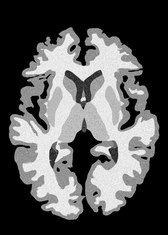

4.2 Registration to a 100 micron ex-vivo brain MRI volume

To showcase the efficacy of our method on real large scale images, we register a 250 in-vivo MRI image (Lüsebrink et al., 2017) to a 100 ex-vivo FLASH human brain volume (Edlow et al., 2019). This represents an inverse problem with more than 11.2B optimizable parameters (compared to 20M for clinical datasets), or 44.8GB of GPU memory. The entire problem does not fit on most GPUs, necessitating distributed multimodal registration. We optimize a composite transform - affine followed by a diffeomorphic mapping; details can be found in Section E.1. Multimodal deformable registration took 58 seconds on 8 NVIDIA A6000 GPUs, which is unprecedented at this resolution. Fig. 6 shows qualitative results, highlighting the ability to register highly detailed structures such as cerebellar white matter; these structures are not visible at macroscopic scales. The resultant advantages of performing registration at this scale can allow researchers to characterize the neuroanatomy at microscopic resolutions and allow morphometric analysis of cortical layers and subcortical nuclei among other structures.